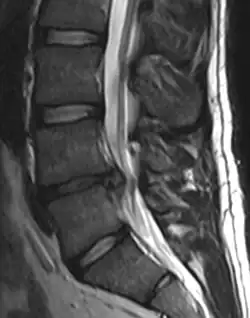

Imaging is indicated when there are red flags, ongoing neurological symptoms that do not resolve, or ongoing or worsening pain.[5] In particular, early use of imaging (either MRI or CT) is recommended for suspected cancer, infection, or cauda equina syndrome.[5] MRI is slightly better than CT for identifying disc disease; the two technologies are equally useful for diagnosing spinal stenosis.[5] Only a few physical diagnostic tests are helpful.[5] The straight leg raise test is almost always positive in those with disc herniation,[5] and lumbar provocative discography may be useful to identify a specific disc causing pain in those with chronic high levels of low back pain.[47] Therapeutic procedures such as nerve blocks can also be used to determine a specific source of pain.[5] Some evidence supports the use of facet joint injections, transforminal epidural injections and sacroiliac injections as diagnostic tests.[5] Most other physical tests, such as evaluating for scoliosis, muscle weakness or wasting, and impaired reflexes, are of little use.[5]

Complaints of low back pain are one of the most common reasons people visit doctors.[48][49] For pain that has lasted only a few weeks, the pain is likely to subside on its own.[50] Thus, if a person's medical history and physical examination do not suggest a specific disease as the cause, medical societies advise against imaging tests such as X-rays, CT scans, and MRIs.[49] Individuals may want such tests but, unless red flags are present,[51][52] they are unnecessary health care.[48][50] Routine imaging increases costs, is associated with higher rates of surgery with no overall benefit,[53][54] and the radiation used may be harmful to one's health.[53] Fewer than 1% of imaging tests identify the cause of the problem.[48] Imaging may also detect harmless abnormalities, encouraging people to request further unnecessary testing or to worry.[48] Even so, MRI scans of the lumbar region increased by more than 300% among United States Medicare beneficiaries from 1994 to 2006.[10]